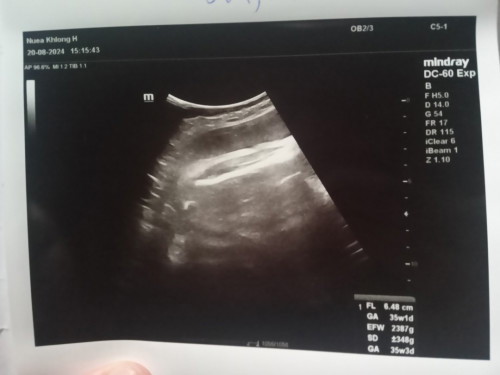

ขอสอบถามหน่อยคะตัวBในใบซาวด์คือเพศลูกใช่มั้ยคะ หรือใครดูเป็นช่วยบอกทีนะคะ

ไม่ใช่ค่ะ